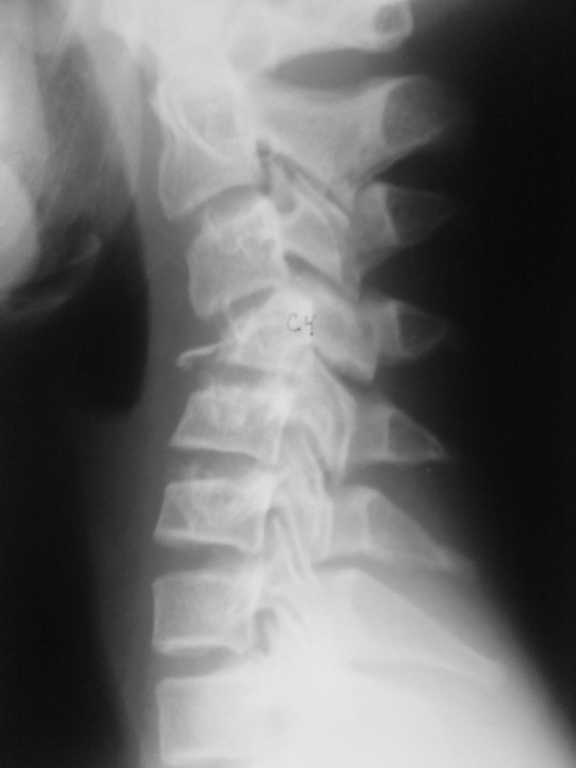

Компрессионный перелом шейного позвонка у подростка

Уважаемые коллеги! Помогите определиться с тактикой лечения. Подросток 14 лет получил травму 2 недели назад , нырнул в реку , вынырнул и на голову прыгнул другой подросток.

Последний госпитализирован в краевую детскую больницу в травматолого-ортопедическое отделение. DS Закрытый нестабильный неосложнённый тип В3 компрессионно- оскольчатый переломо-вывих С4, перелом обеих дужек, перелом сутавного отростка, двухсторонний сцепившийся вывих С4. При поступлении наложен галоапппарат, проводилась галотракция. Представлены Rg-снимки до и после галотракции. Необходимо решить вопрос : необходим ли передний корпородез если да , то когда?

Больному выполнена Rg- ШОП, КТ_ до галотракции, после галотракции.

Уважаемый Вячеслав! Для определения тактики лечения необходимо: Спондилограммы в двух проекциях, до и после Ваших манипуляций, КТ, по возможности и МРТ. В каком состоянии CV и CVI? Вероятно, имеется стеноз позвоночного канала на уровне CIV, который придется устранять.

Мы бы выполнили переднюю декомпрессию, открытое вправление вывиха и передний расклинивающий спондилодез (кифоз после полноценной резекции тела удастся устранить) CIII-V + пластинка.

Судя по тексту сообщений нам представлены результаты исследований до и после галотракции. Их не вижу только я или и еще кто-то? По боковой рентгенограмме и реконструкции КТ спорить о тактике лечения и объеме операции бессмысленно.